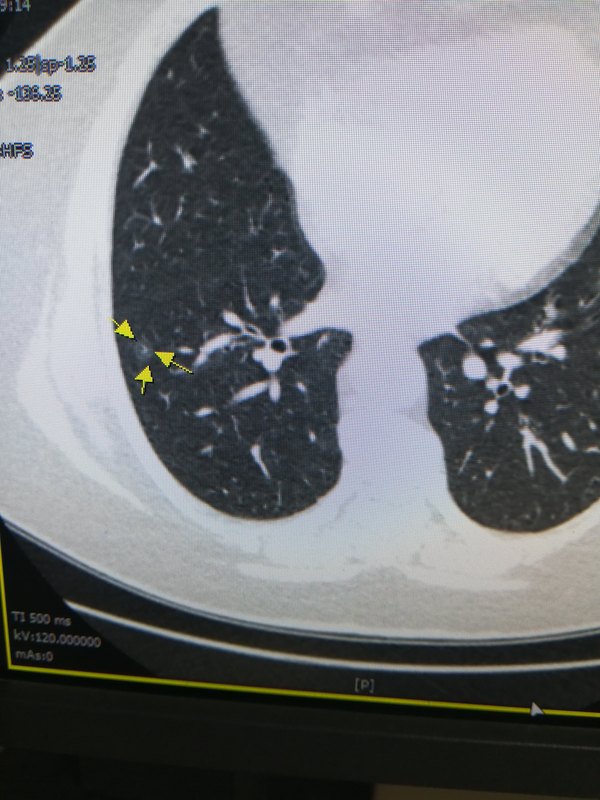

患者女,53岁,查体发现纯磨玻璃结节,直径约14mm,平均CT值约-200HU,可见增粗血管。 没有引起重视,持续随访。4个月后。 考虑浸润性腺癌,患者还是没有重视。 两年后,病灶明显增大,实性成分明显增大。 血管移动联通。 纯磨玻璃肿瘤性磨玻璃结节,惰性生长,随访是安全的,但需要风险评估。所以,病灶超过1CM,纯磨玻璃结节,出现实性成分,病灶进展,影像考虑浸润性腺癌,见到血管移动联通要及时手术,避免延误治疗!

磨玻璃结节随访增大就需要手术?所谓增大指体积增大,测量直径增大。肺纯磨玻璃结节7mm,影像倾向原位癌,一年半后病灶增长病灶为11mm,影像还是倾向原位癌,观察还是手术?病灶虽然增大了,仅仅是体积增大,不是密度增高(密度逐渐增高,代表病灶向微浸润进展),还是原位癌,它的增大是在原位癌基础上的增大,还可以随访的!什么样的磨玻璃结节增大需要及时手术?混合磨玻璃结节浸润性腺癌和微浸润腺癌阶段,纯磨玻璃结节浸润性腺癌阶段需及时干预,所以需要精准诊断判断病理亚型精确指导临床! 一年半后病灶增大